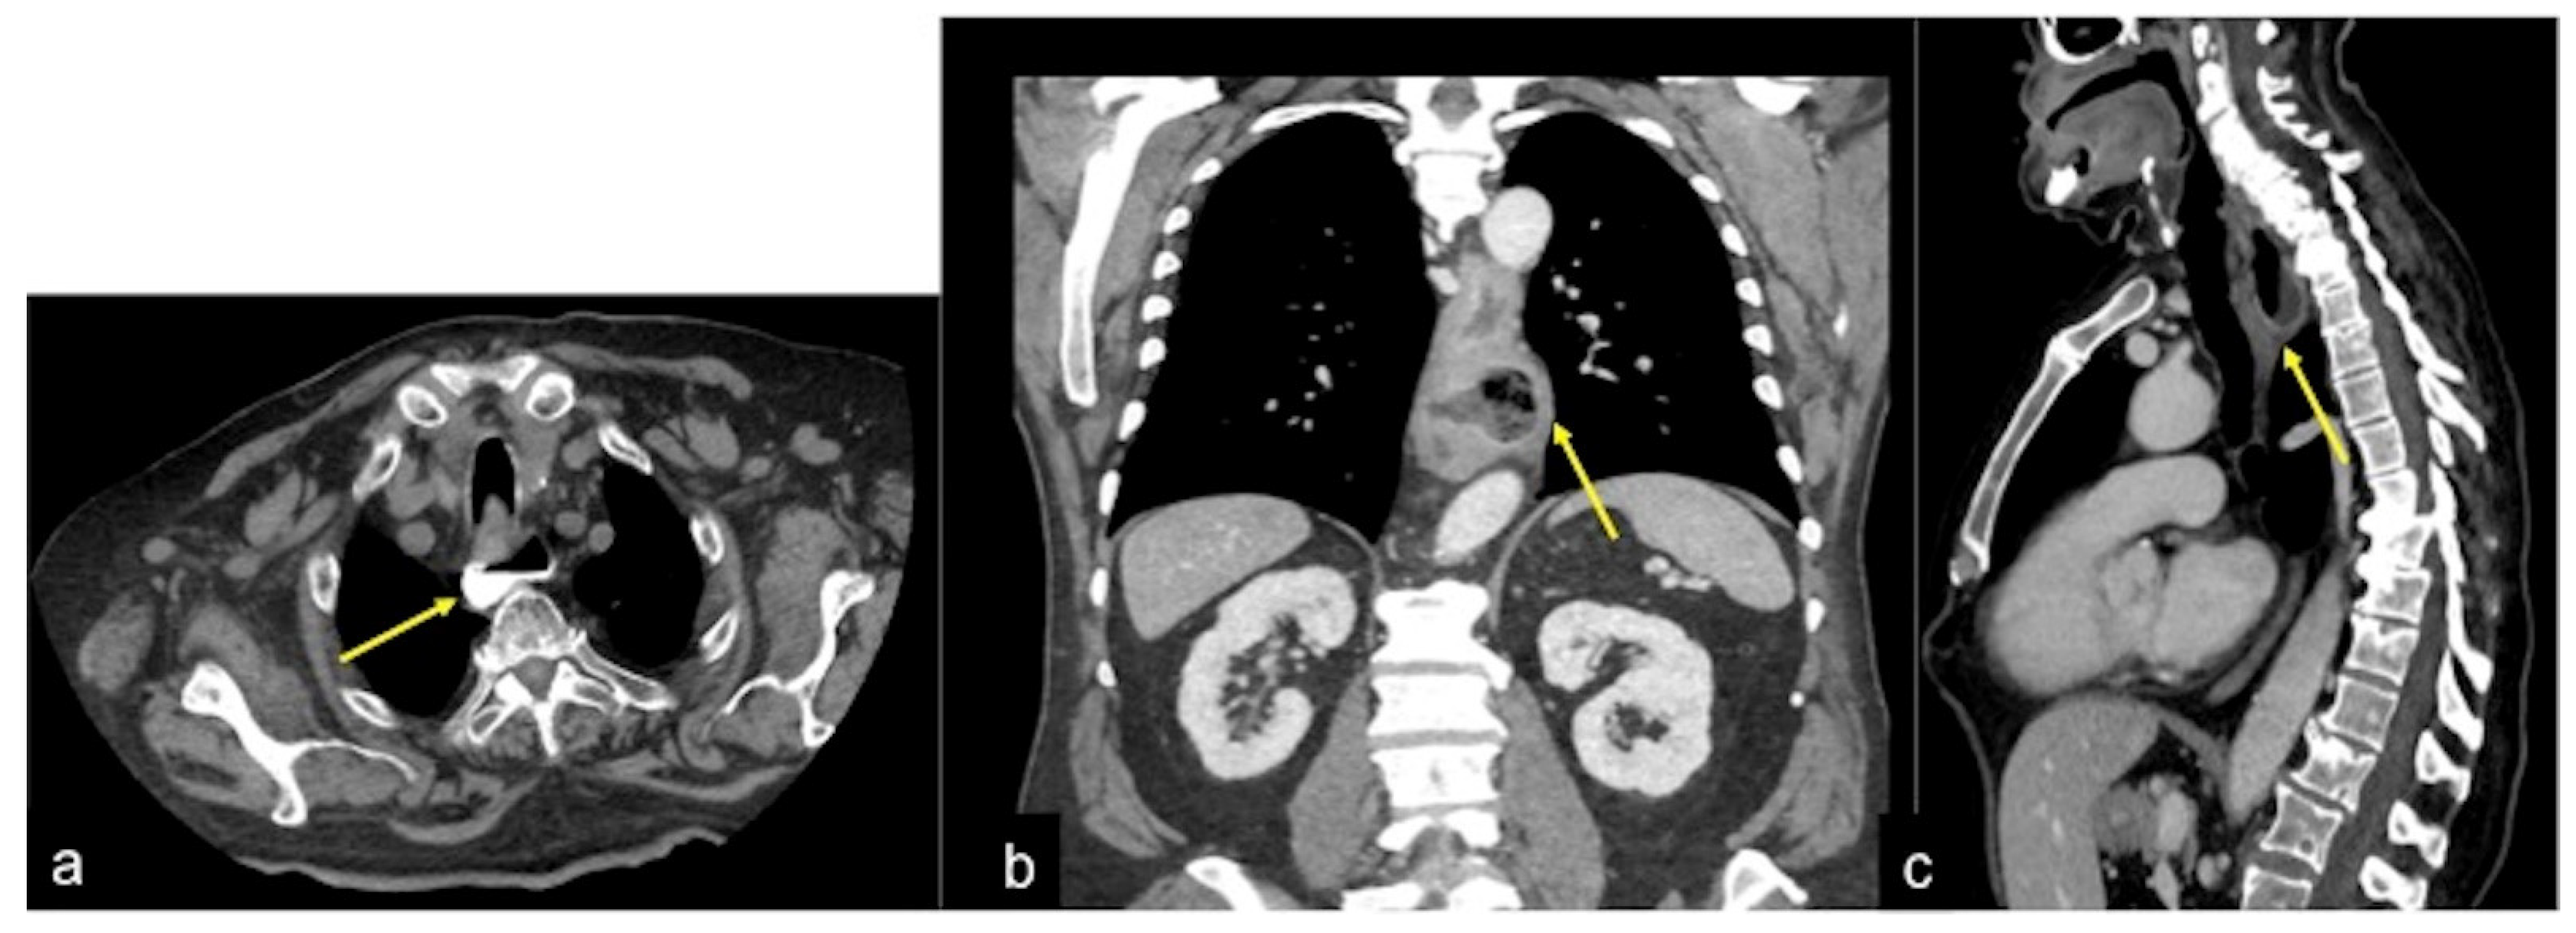

| Oesophageal-gastric varices due to portal hypertension (Figure 21) | Asymptomatic until they rupture in the oesophageal lumen and cause haematemesis or melaena or haematochezia depending on the severity of the bleeding. | Tortuous, enlarged, smooth tubular structures protruding into the oesophageal lumen or adjacent to the internal oesophageal mucosa. |